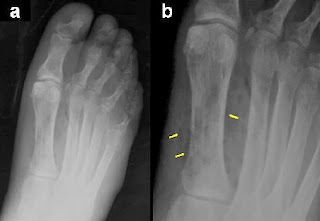

| Radiografía de pie diabetico |

- Aparición de cuerpo extraño

- Existencia de gas en el espacio tisular

- Aumento de partes blandas secundario a edema

- Contraste con aire de la úlcera

- Calcificaciones arteriales (arteria pedia, plantar y tibial posterior)